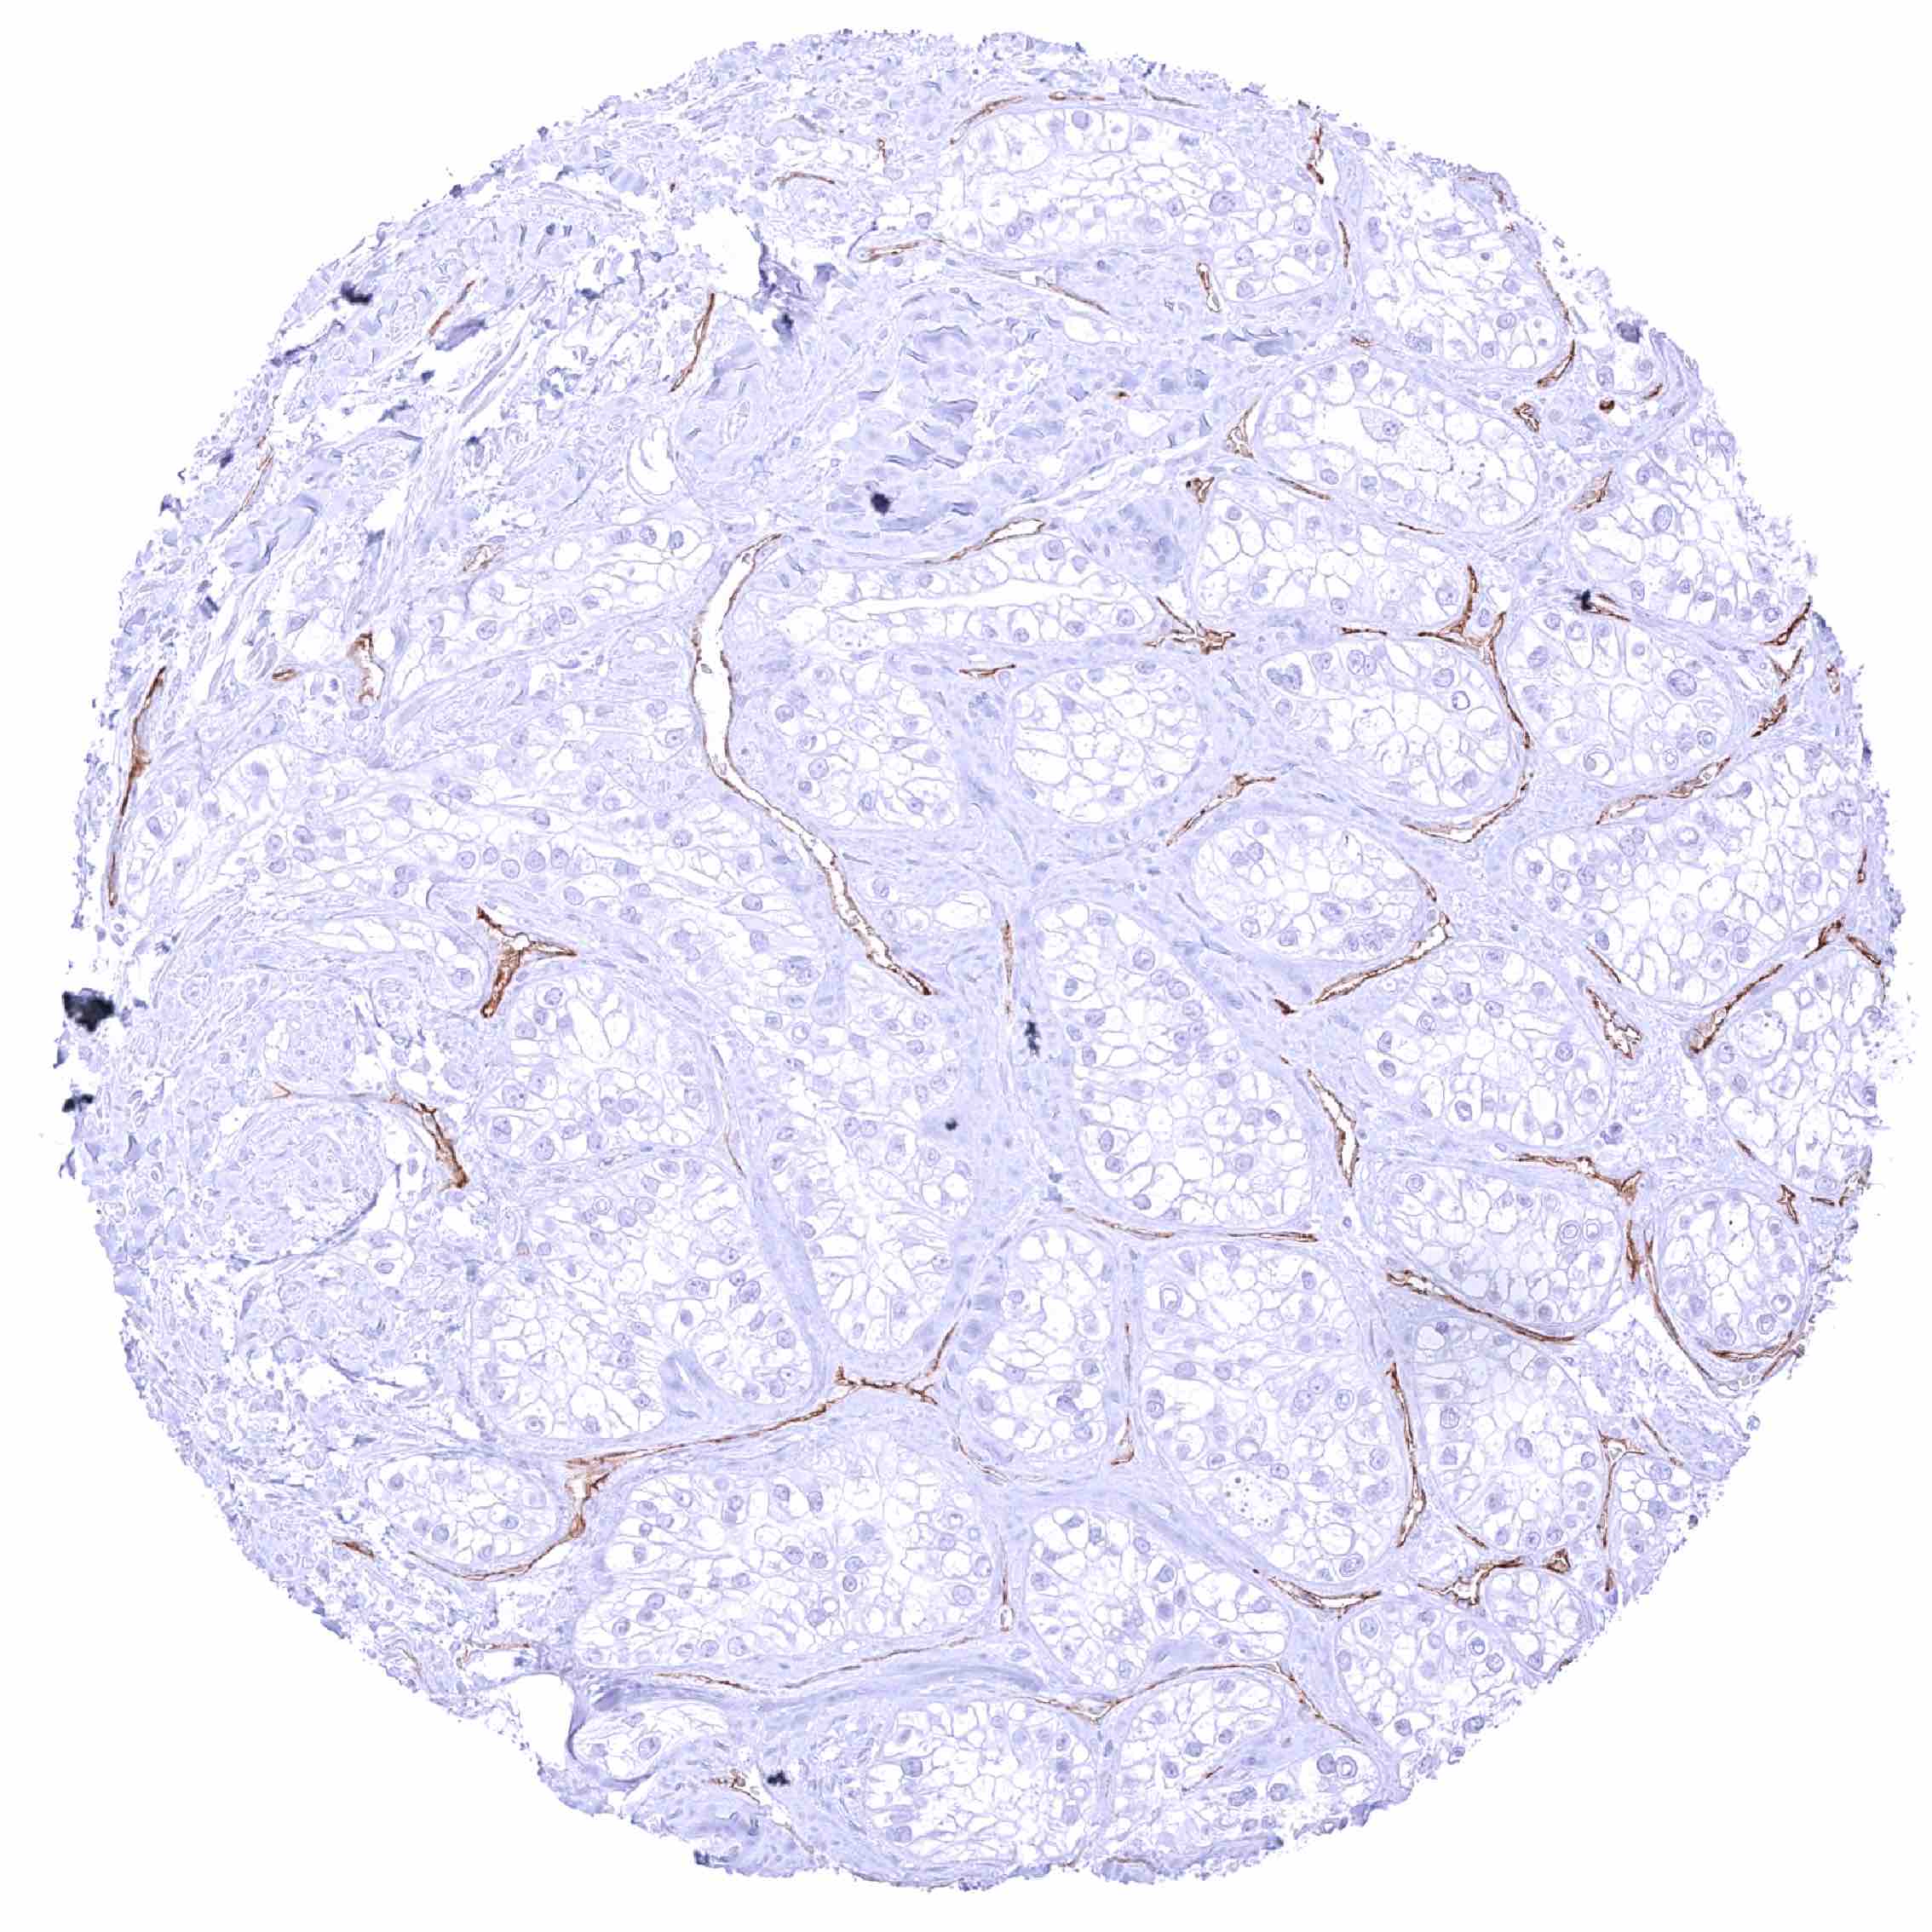

Colon – Colorectal adenocarcinoma with moderate to strong, partly “dot-like”, partly membranous PODXL immunostaining of tumor cells. Distinct PODXL positivity of endothelial cells of tumor associated vasculature